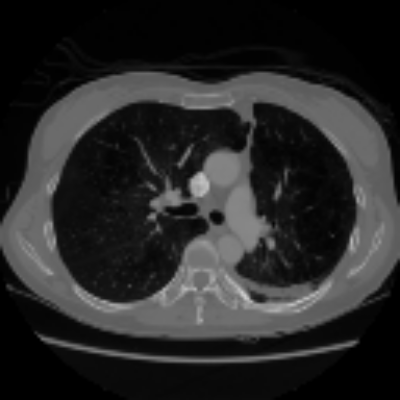

| Axial | Coronal | Sagittal | |

| X2CTGAN | ![]() |

![]() |

|

| DX2CT | ![]() |

| Ground-truth | ![]() |

Figure 3 and Table I(a) using biplanar X-rays show that proposed DX2CT can outperform three existing SOTA methods. Figure 3 shows that DX2CT can provide more accurate overall shapes and details compared to the existing methods. The quality of reconstructed CT slices in the axial plane is less satisfactory than those in the other planes. The reason is that the axial plane is perpendicular to the planes of biplanar X-rays so there exists less spatial (i.e., depth) information in the axial plane. Without using the perceptual loss [33], proposed DX2CT gave comparable LPIPS results with PerX2CTs using [33] in training. Compare their LPIPS results in Table I(a).